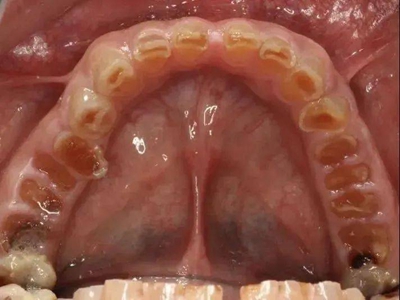

牙釉质发育不全牙齿上棕色的坑图

牙釉质发育不全程度严重时,牙齿上出现较深的条状、点状凹陷,内含深褐色物质,并且牙齿尖端的牙釉质缺失,牙齿变得相对脆弱。

牙釉质发育不全牙齿棕色有缺损图

牙釉质发育不全患者牙齿出现明显的缺损表现,并于表面形成深褐色的蜂窝状、竖条状的凹坑,甚至形成洞,患者上下牙失去咬合能力。